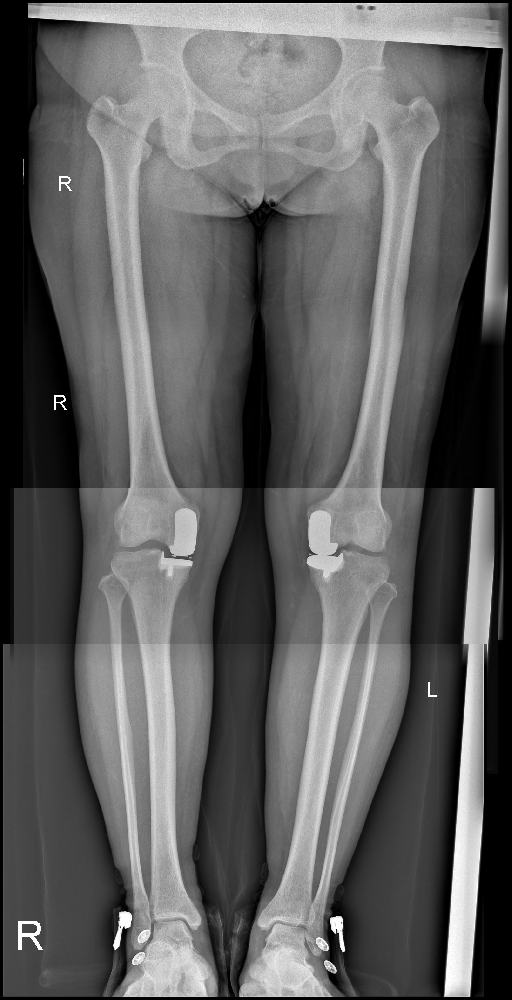

李娜,一個(gè)45歲的女性,居住在市中區(qū)齊村鎮(zhèn)尖山子村。她因?yàn)殡p膝間斷疼痛已有8年之久,最近終于決定入院治療?;颊咦允霭Y狀發(fā)生在8年前,當(dāng)時(shí)并沒有明顯的誘因,雙膝開始出現(xiàn)疼痛。這種疼痛是間斷性的,勞累后疼痛會(huì)加重,但休息時(shí)可以緩解。尤其是在負(fù)重時(shí),疼痛感更為明顯。

在這8年的時(shí)間里,患者曾嘗試過口服活血止痛類藥物等治療方法,初期確實(shí)有一定的效果,癥狀得以緩解。然而不久之后,疼痛又重新出現(xiàn),讓患者倍感困擾。為了尋求更徹底的治療,李娜決定前往市中區(qū)誠(chéng)德骨科醫(yī)院住院,并接受進(jìn)一步的檢查。

在住院期間,醫(yī)生為她進(jìn)行了全面的檢查,并選擇了適合她的治療方式——雙膝關(guān)節(jié)內(nèi)側(cè)活動(dòng)平臺(tái)單髁置換術(shù)。術(shù)后,李娜的康復(fù)情況良好。她逐漸恢復(fù)了原本健康的雙膝,再次能夠正常行走和負(fù)重。

圖片1.png